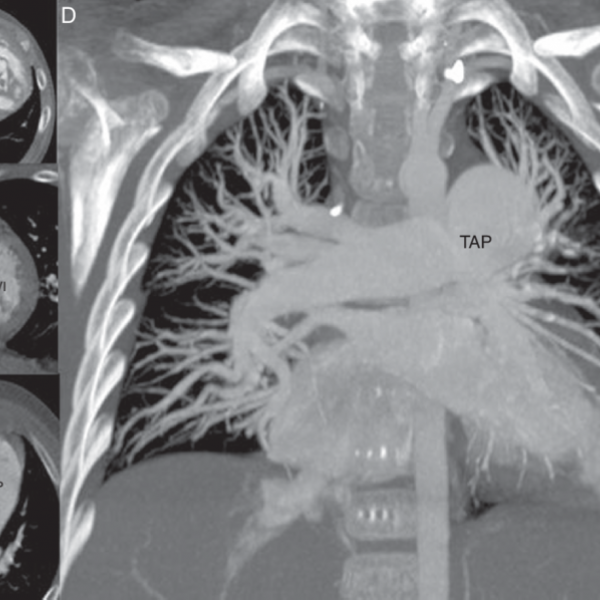

Angiotomografia de arterias pulmonares. 879901. Idime. (2022)

INCLUYE MEDIO DE CONTRASTE